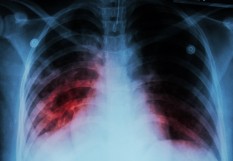

La tuberculose en légère augmentation en France

A l’occasion de la Journée mondiale de lutte contre la tuberculose ce lundi 24 mars, Santé publique France (SPF) publie les dernières données épidémiologiques sur cette infection. Il en ressort une légère remontée de l’incidence en 2023 sans impact significatif sur les formes graves. Ainsi, en 2023, les nouveaux cas de tuberculose étaient en augmentation de 16,7% par rapport à l’année précédente en France, avec 4 866 cas déclarés. Cette hausse est d’autant plus marquante qu’elle succède à plusieurs années (depuis 2020) de baisse liée au Covid.

"La tendance en 2023 reflète probablement, après une baisse régulière pendant trois ans, un retour à une situation pré-pandémique. Il est cependant nécessaire de rester vigilants afin de confirmer qu’il s’agit bien d’une hausse ponctuelle liée à des circonstances exceptionnelles et non pas d’une augmentation liée à une intensification de la transmission du bacille tuberculeux au sein de la population", explique SPF.

Les régions les plus touchées par la tuberculose sont la Guyane (24,0/100 000), l'Île-de-France (14,2) et Mayotte (12,8), qui présentent des taux de déclaration bien supérieurs à la moyenne nationale (7,1/100 000).

En revanche, la hausse de l’incidence n’a entrainé que peu d’impact sur les formes graves de la maladie (méningées et miliaires) et les cas de tuberculoses multi-résistantes, qui représentent 5,9% des cas ; ce qui est peu près stable par rapport aux années précédentes (5,7 % en 2022 et 5,4% en 2019). Le nombre de décès en rapport avec l’infection est en légère augmentation, passant de 22 en 2022 à 30 en 2023, "mais cela reste dans des proportions relativement faibles (0,6% des cas) et inférieures aux niveaux prépandémiques", souligne SPF. Elle conseille néanmoins de poursuivre la surveillance pour "confirmer que la pandémie de Covid n’a pas eu d’impact négatif sur la sévérité de la maladie".

Par ailleurs, contrairement à d’autres pays européens, on n’observe pas en France de hausse chez les enfants. Et ce, malgré la suppression de l'obligation vaccinale par le BCG il y a 15 ans.  Ainsi, il y a eu, en 2023, 13 formes graves de tuberculose chez des enfants de moins de 15 ans, dont trois en Île-de-France. "Ce nombre reste stable autour de 10 cas par an depuis cinq ans et correspond aux prévisions émises lors de la suspension de l'obligation vaccinale BCG", précise SPF.